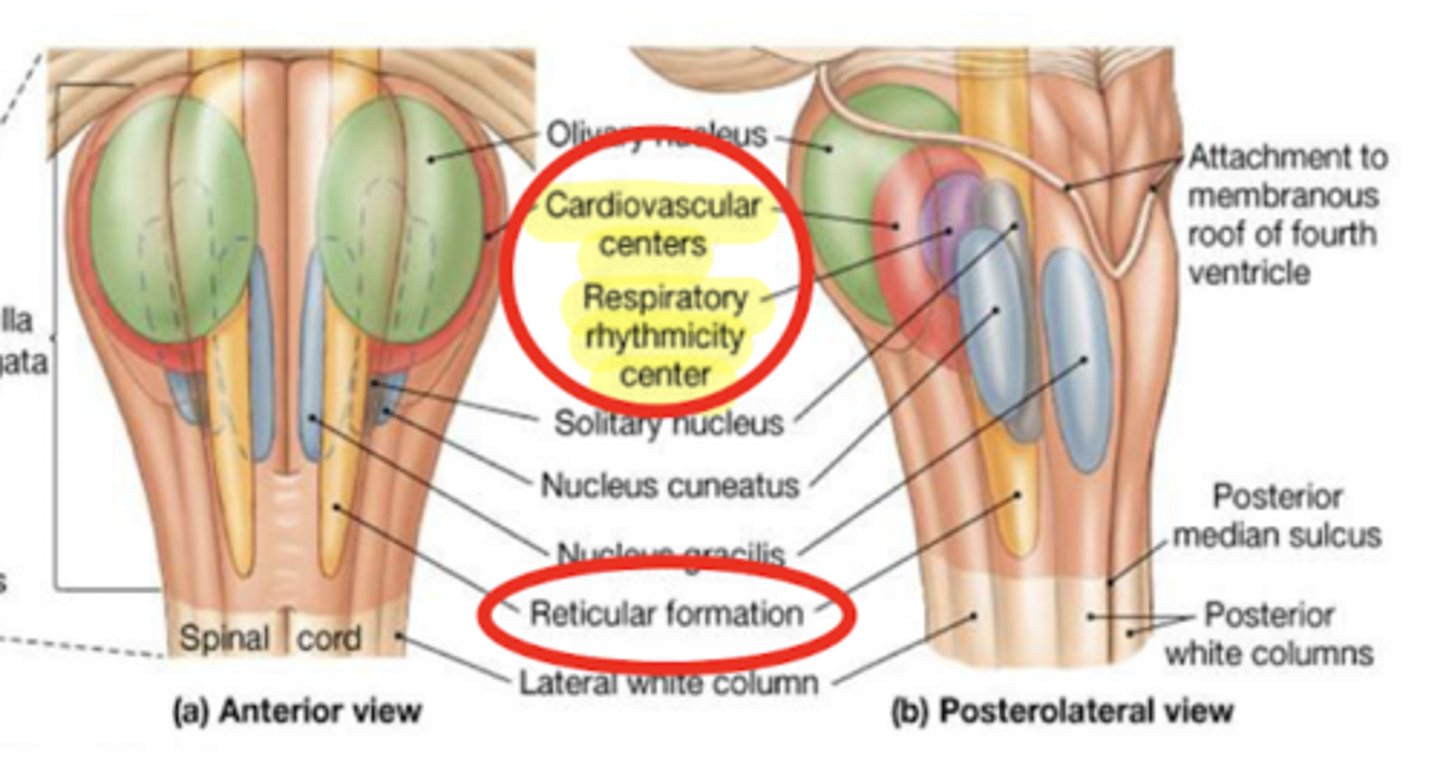

What is the descending phenomenon of comas?

superficial coma -- cortex that is not working (cerebral hemisphere)

deep coma (worst) -- cortex + brain structures

if coma reaches the medulla it can hit the respiratory center, requiring life support

Where does the 4th ventricle end?

medulla

cranial medulla -- "open" half

caudal medulla -- "closed" half